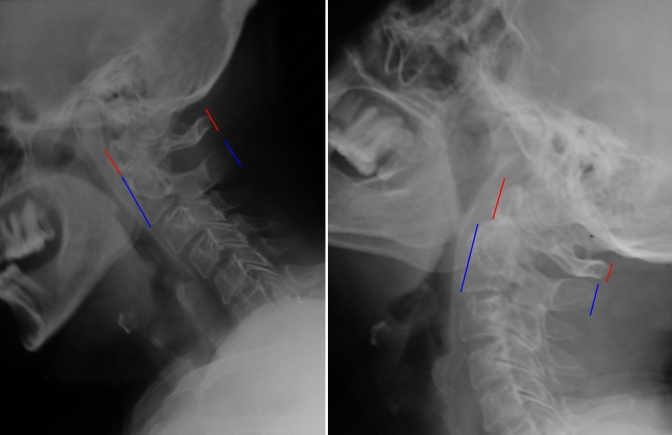

Fonksiyonel Servikal Grafi - İnstabilite

Resim 4: Fleksiyon / ekstansiyon grafilerinde atlasın ekstansiyonda hafifçe geriye kaydığı görülmektedir (=atlanto-aksiyal instabilite). Ayrıca, fleksiyon grafisinde C3-C4 ve C4-C5 mesafelerinde hafif kaymalar mevcuttur.